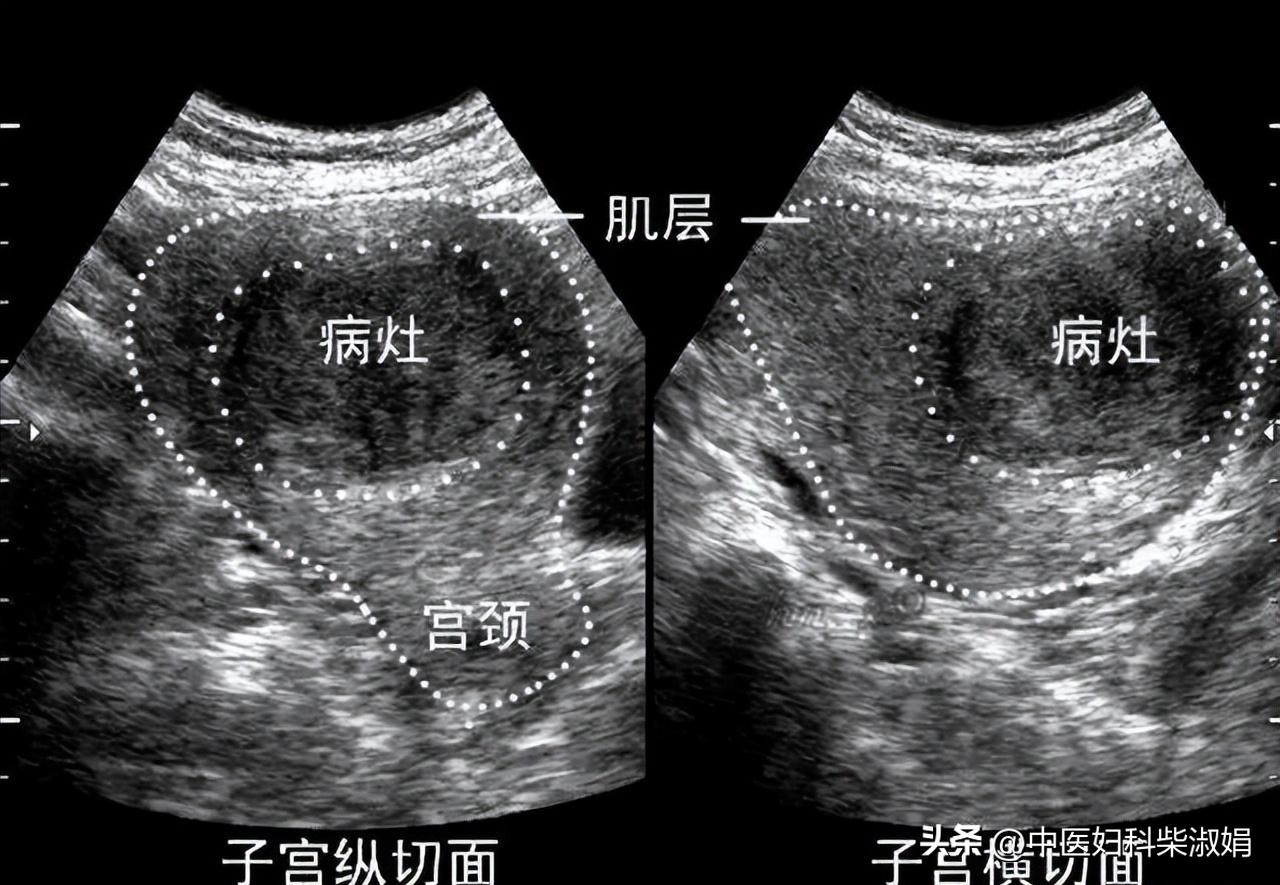

► 棘手的定时*弹炸**——子宫肌瘤

育龄期的妇女比较容易发现子宫肌瘤,子宫肌瘤这个病,其实90%都是良性的,不过这个病确实给女性带来很多困扰。

子宫肌瘤会出现月经异常,比如痛经、月经不调、有血块;白带增多;腹部出现肿块,可能伴有疼痛;还易引起不育及流产;如果肌瘤压迫到直肠、膀胱,可能会导致尿频、尿急、排便困难。

没想到还不到半年,检查出子宫肌瘤复发了,而且生长速度比较快,已经达到了3cm。

四诊检查显示肌瘤缩小了1.2cm。根据调理情况,调整了药方。